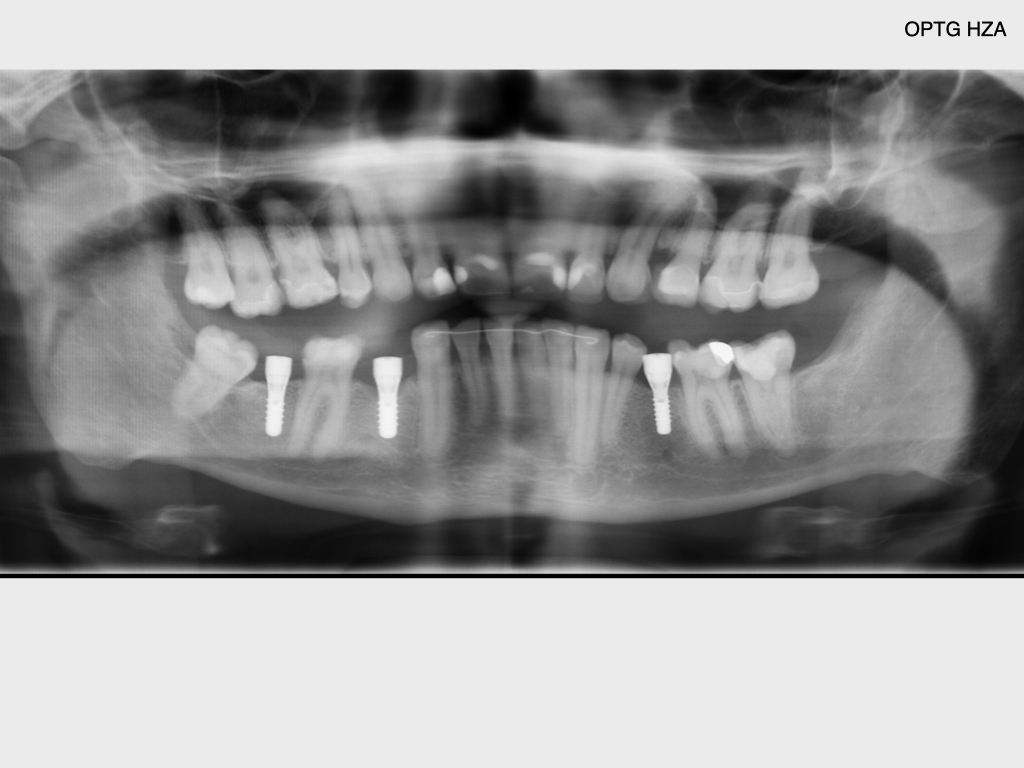

Krampf und Kampf